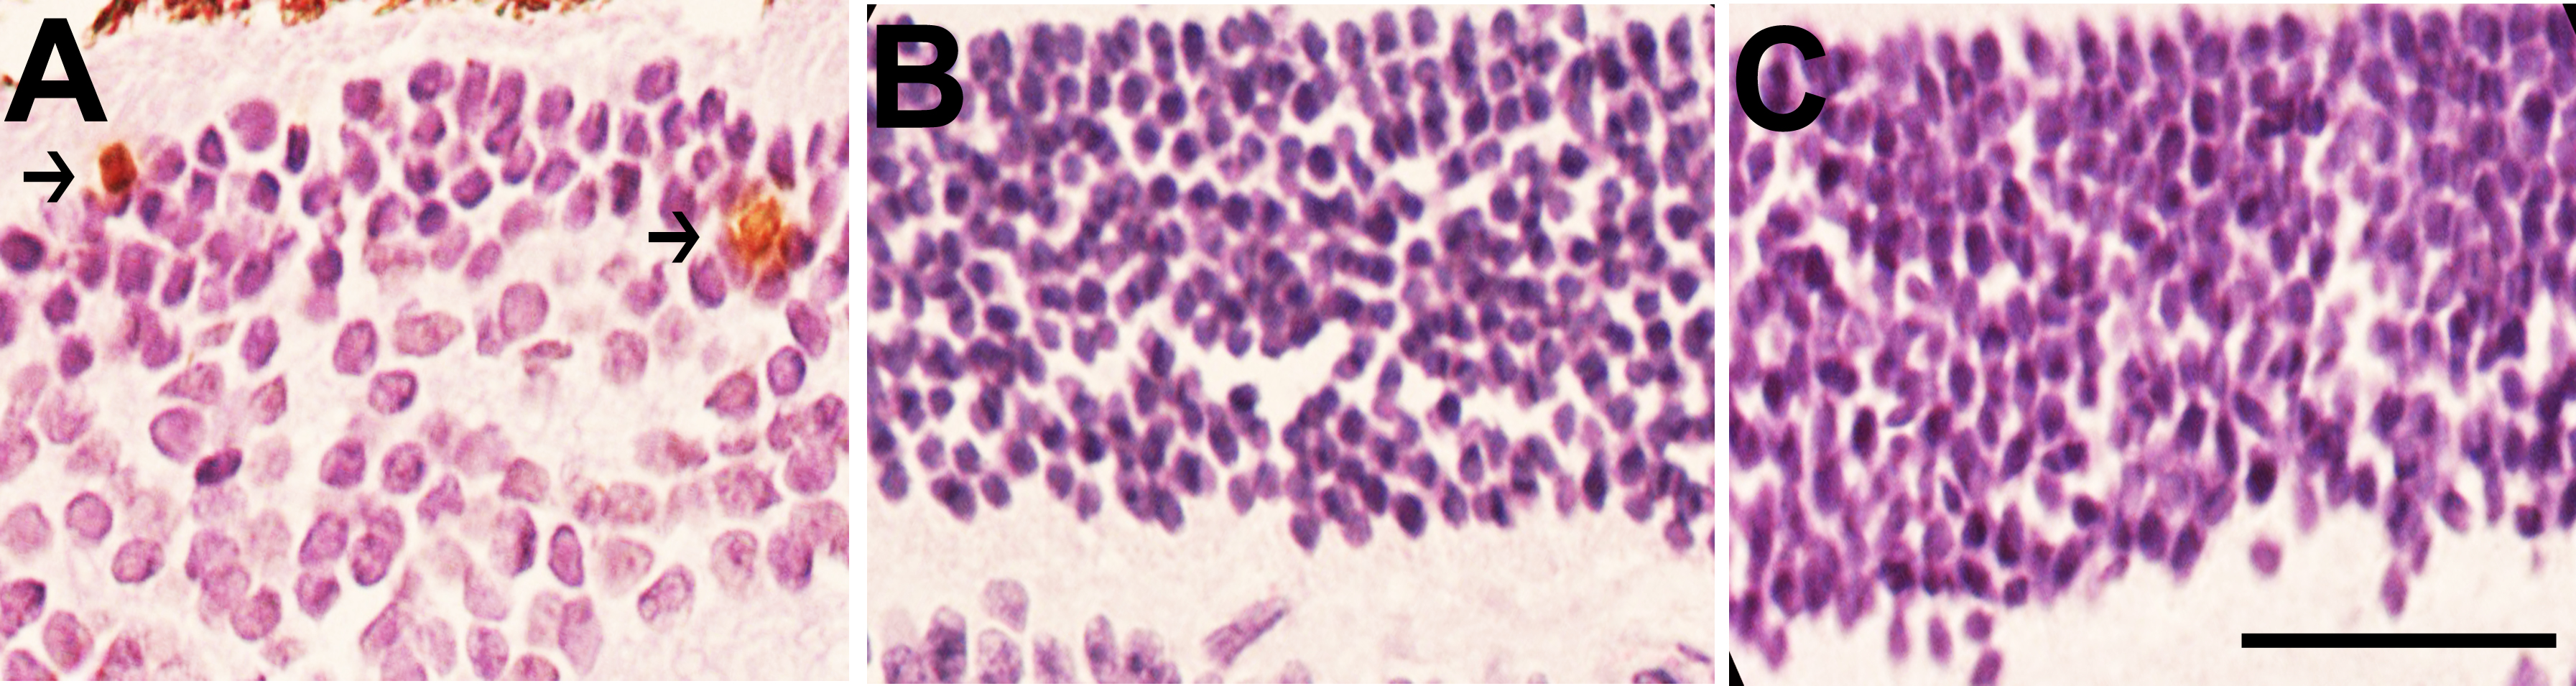

Figure 4. Apoptotic cells in the retinal layers of 15-month-old mice. Terminal deoxynucleotidyl transferase dUTP nick end labeling (TUNEL)

showed apoptotic cells (arrows) in the outer nuclear layer (ONL) of low-density lipoprotein receptor–deficient apolipoprotein

B-100-only mice overexpressing insulin-like growth factor II (IGF-II/LDLR–/–ApoB100/100). A: No positivity was found in the LDLR–/–ApoB100/100 mice (B) or C57Bl/6J mice (C). Original magnification in the figure is 400×, and the scale bar is 25 μm.